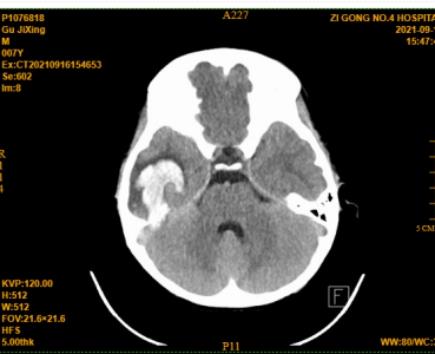

“医生、医生,快看看,我娃儿既没有摔斗,又没有碰斗的,咋子突然的喊脑壳痛,还吐了安?”在自贡市第四人民医院神经外科,一位七岁男孩的家长焦急的询问着。头颅CT发现,这位小朋友是右颞叶脑出血,破溃入蛛网膜下腔。那正如这位家长所说,这个娃娃既然没有磕着碰着,怎么会有脑出血?进一步行头颅CTA检查(一种无创的CT脑血管造影检查),发现右颞一动静脉畸形,原来引起儿童出血的罪魁祸首是---脑动静脉畸形。

术前CT